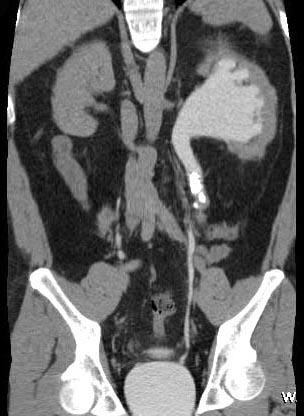

问题 男,42岁,反复左侧腰部疼痛伴血尿3个月余,CT检查如图,下列说法错误的是 ( )

选项 A、左输尿管结核并左肾积水 B、考虑为左输尿管结石并积水 C、左侧输尿管上段扩张 D、左侧肾盂肾盏扩张 E、左侧输尿管内可见多发的高密度影

答案 A